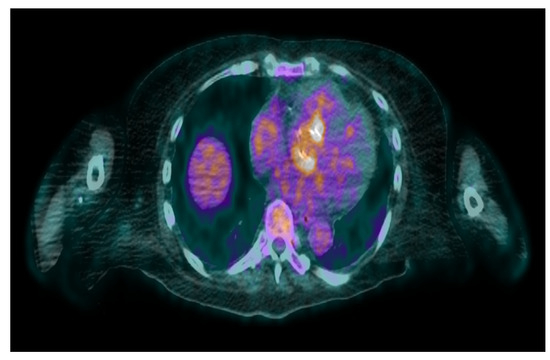

- Uncovering hidden infectious spread: FDG-PET/CT can also detect clinically silent disseminated infectious disease, identifying primary infection source, and/or septic embolism, which can be crucial for diagnosis and guiding patient management.